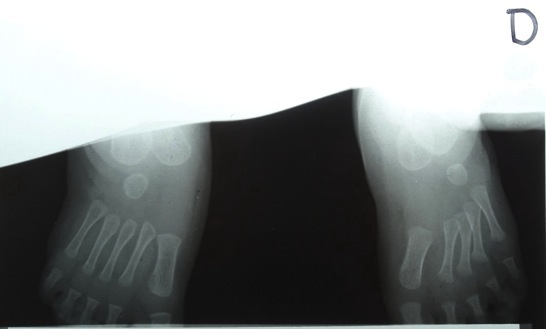

Analyse de radiographies

Analyse différentes radiographies. Essaye de reconnaître:

les différentes parties représentées: os, articulations,...

les malformations, les déplacements, les fractures.

l’âge des sujets: zones de croissances.